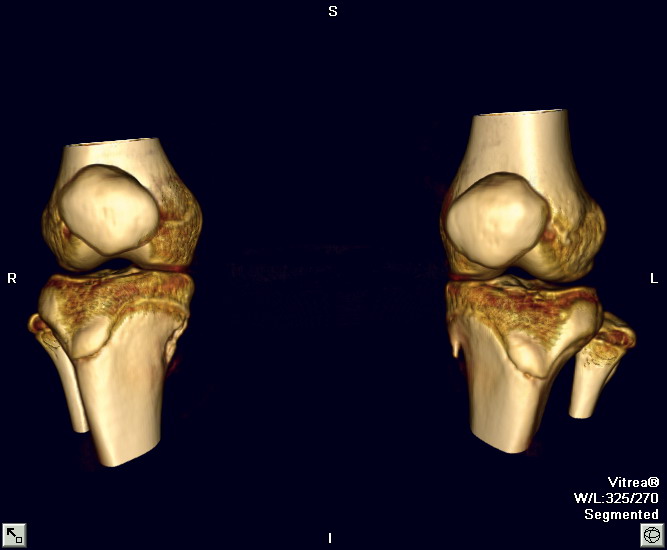

以下是引用zxl51642在2010-2-20 14:49:00的发言:[br]1)左胫骨近端干骺端外生骨疣,同意。[br]2)右胫骨纤维骨皮质缺损?不同意。[br]fcd无软组织肿块,是否可考虑软组织病变如骨膜软骨瘤、骨膜硬纤维瘤、神经纤维瘤之类的病变,给平片和ct轴位像。

以下是引用zxl51642在2010-2-20 14:49:00的发言:[br]1)左胫骨近端干骺端外生骨疣,同意。[br]2)右胫骨纤维骨皮质缺损?不同意。[br]fcd无软组织肿块,是否可考虑软组织病变如骨膜软骨瘤、骨膜硬纤维瘤、神经纤维瘤之类的病变,给平片和ct轴位像。